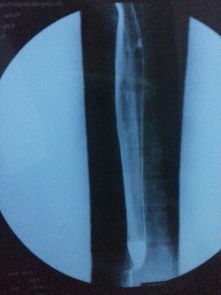

為了保證檢查準(zhǔn)確,做食道鋇餐檢查早晨不能吃飯喝水,包括肝功,血脂,血糖等檢查也是這樣要求的.X線鋇餐檢查 食管X線鋇餐檢查可顯示鋇劑在癌腫點(diǎn)停滯,病變段鋇流細(xì)窄;食管壁僵硬,蠕動(dòng)減弱,粘膜紋變粗而紊亂,邊緣毛糙;食管腔狹窄而不規(guī)則,梗阻上段輕度擴(kuò)張,并可有潰瘍壁龕及棄盈缺損等改變。

常規(guī)X線鋇餐檢查常不易發(fā)現(xiàn)淺表和小癌腫。應(yīng)用甲基纖維素鈉(sodium methyl cellulose)和鋇劑作雙重對(duì)比造影,可更清楚地顯示食管粘膜,提高食管癌的發(fā)現(xiàn)率。